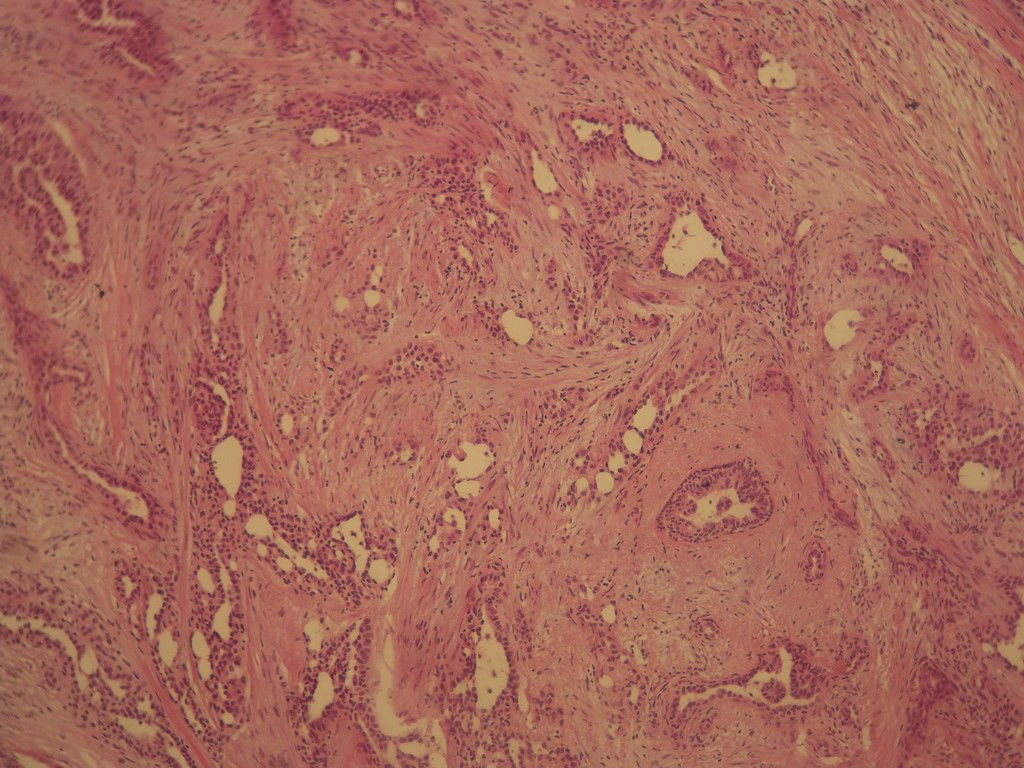

B3806腺病?癌?其他?(12楼常规,24楼免疫组化及会诊结果)

今天的一例术中冰冻。女,49岁,乳腺肿块。人气不旺,换个标题

标签:浸润性导管癌 分泌癌 硬化性腺病

乳腺分泌型癌

Difficult to say it is IDC in frozen

浸润性导管癌